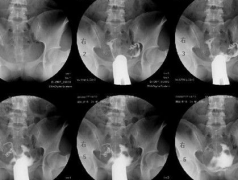

输卵管造影被广泛的应用于输卵管疾病的检查中,输卵管造影是通过导管向女性的子宫腔,输卵管注入……